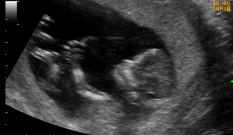

Se, por alguma razão, fosse feito um ultrassom vaginal de alta resolução, seria possível observar muitos detalhes do feto, como o cristalino dentro dos olhos e as válvulas do coração, e contar seus dedos quando abre a mão.